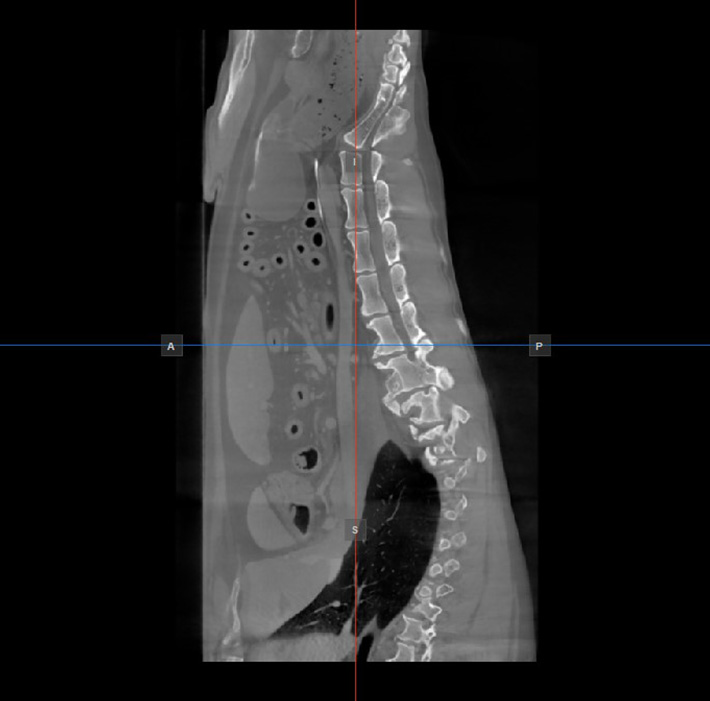

Image Orientation and Image Planes¶

The position and intersection of the other two image planes not represented in the active viewport is indicated by two vertical and horizontal lines called slicers. The endpoints of each slicer are labeled with a letter that corresponds to the appropriate direction/side of the 3D volume, based on the RAS coordinate system.

Only four sides of the available six are indicated on each 2D viewport. The labels and the corresponding side are the following:

Patient Right (R), indicating the right side of the body

Patient Left (L), indicating the left side of the body

Anterior (A), indicating the front side of the body

Posterior (P), indicating the back side of the body

Superior (S), indicating the top side of the body

Inferior (I), indicating the bottom side of the body